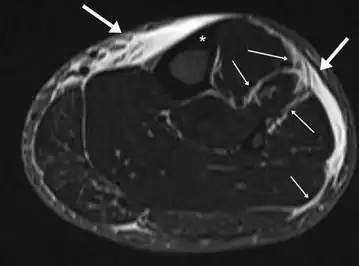

MRI of the left lower leg-severe “shin-splint”

Magnetic resonance image of the lower leg in the coronal plane showing high signal (bright) areas around the tibia as signs of shin splints.